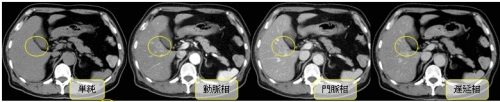

造影剤という薬を注射してから撮影を行います。撮影する部位や方法の違いで、何回か撮影することがあります。また、血管の3D撮影も行います。通常は、単純CTを撮影したあと造影剤を注射して造影CTを行いますが、造影CTのみの場合もあります。

造影剤が入ると血管や腫瘍などがはっきりと写るようになります。

○で囲まれたところに単純画像ではわかりませんが、造影剤が入ると白く映ります。